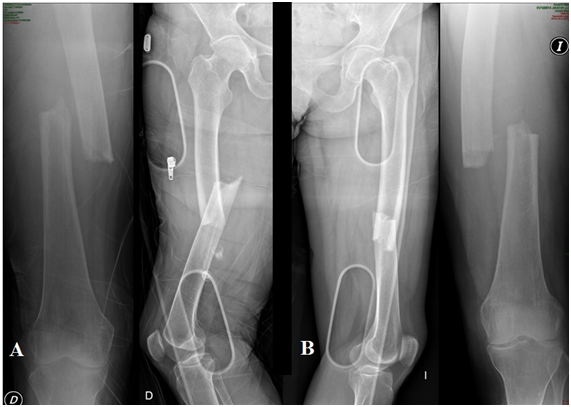

The patient was admitted to the common room and bilateral trans-tibial skeletal traction was performed. The reduction and osteosynthesis was performed on the same day of the accident, the patient was operated on a traction table and the osteosynthesis was performed on both femurs with milled intramedullary nails (Synthes universal nail). Osteosynthesis was performed first of the left femur and then the right one (Figure 3). Immediate partial load was indicated with the use of crutches. The use of alendronate was discontinued, it was indicated to continue with vitamin D and no other medication was added.

Figure 3 Immediate post-surgical radiographs.

The consolidation of the right femur was completed at 11 months, no longer had pain or discomfort in the femur but continued with pain in the left thigh, new radiographs were made showing hypertrophic pseudoarthrosis so it was decided to perform a new surgery and place a plate blocked with minimally invasive technique on the nail, with this procedure immediate pain relief is achieved, full load was allowed after 2 weeks and consolidation was achieved 3 months later (Figure 4). Currently, the patient is 2.5 years old and does not present any pain or limitation in hip and knee mobility (Figure 5).

Figure 4 A) 6 months PO. B) 11 months PO: consolidation femur der. Plate MIO femur left.